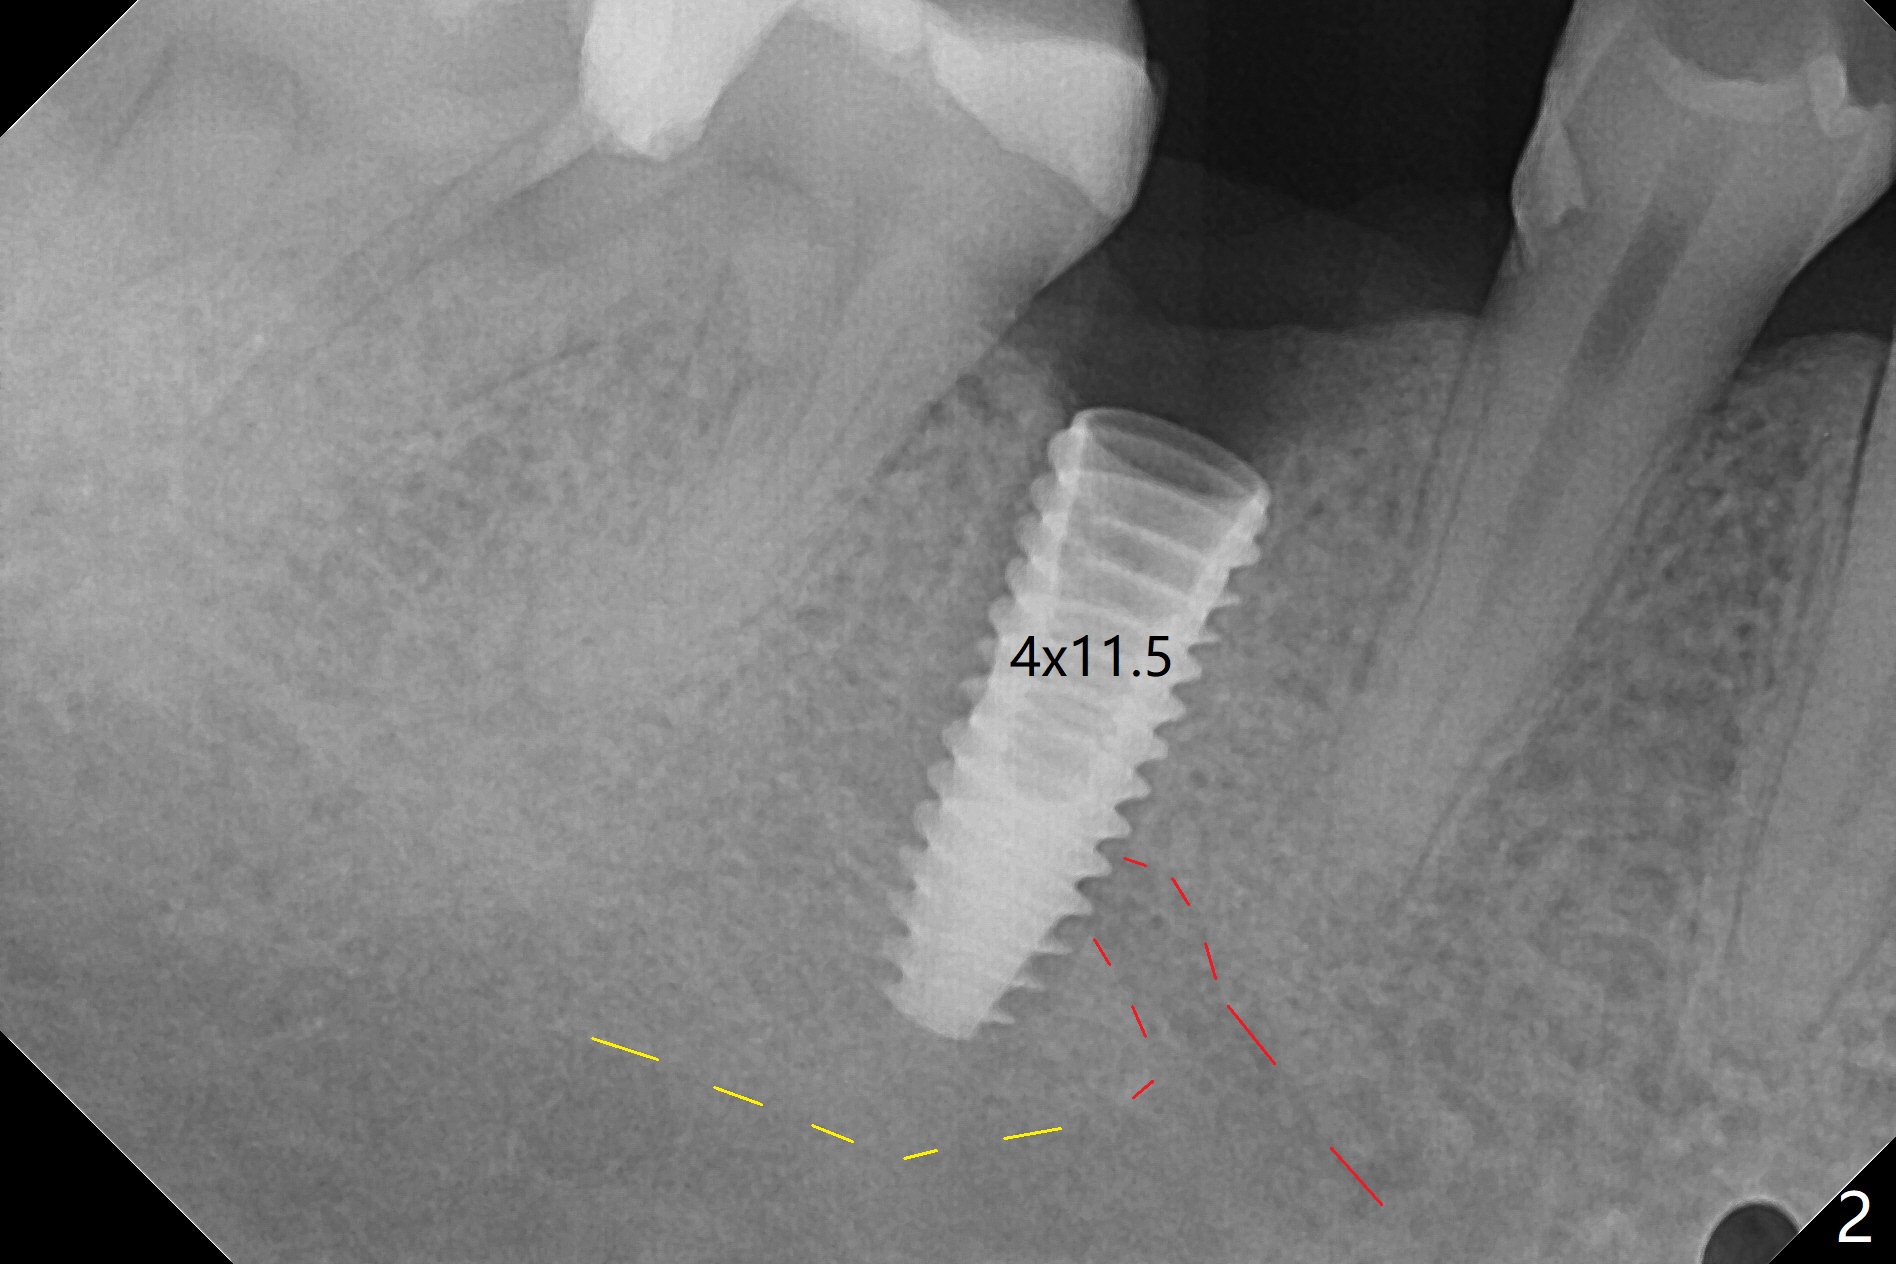

Osteotomy starts in the lingual slope of the socket of #29 with Point/Lindamann bur, but a little too distal. Gradually the osteotomy is moved mesial; the trajectory and position (Fig.1) are better than designed, but the osteotomy is close to the Mental Loop (red dashed line). When a 4x11.5 mm implant is placed, it appears to overlap the buccally positioned Loop (Fig.2 red dashed line). In fact there is no postop paresthesia. The implant placement level seems to be ideal (Fig.3 after bone graft). There is foul smell from the immediate provisional; in fact it may be due to the loose contact between the implant and abutment (Fig.4 < (4 months postop)). The gingiva is unhealthy. A 5.5x5 mm healing abutment is placed. When the patient returns 5 months postop, the gingiva is healthy after removal of the healing abutment. A 4.5x4(4) mm cemented abutment is seated without interference and torqued to 35 Ncm (Fig.5).